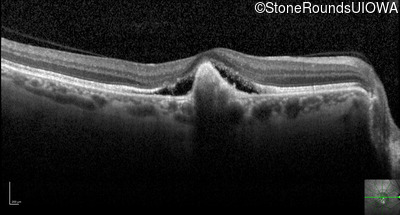

Optical Coherence Tomography - Right - 20/25 -2

Exemplar / OCT Stack